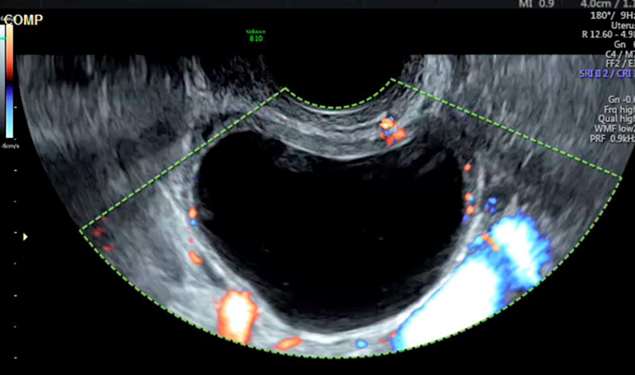

Il n’y a pas de vascularisation périphérique anarchique sur cette image. Le gros vaisseau prenant le signal Doppler correspond à l’artère iliaque interne.

L’échographie pelvienne est la suivante (fig. 4).

Figure 4 (Rodolphe Matias de Sousa, La Revue du Praticien)

Question 6 - Quelle est votre interprétation (une ou plusieurs réponses exactes) ?

Cliniquement, l’hypotension, la tachycardie et les vertiges doivent faire évoquer un saignement actif. À l’échographie, il y a en effet un épanchement abondant dans le cul-de-sac de Douglas remontant jusqu’à l’espace de Morrison.

La douleur brutale post-rapport sexuel, l’instabilité hémodynamique, l’aspect d’hémorragie intra-kystique avec cet aspect hétérogène « en toile d’araignée » du kyste et l’hémopéritoine doivent faire évoquer une rupture hémorragique du kyste.